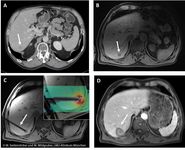

TK Heft 6/2025 Management von Tumormetastasen